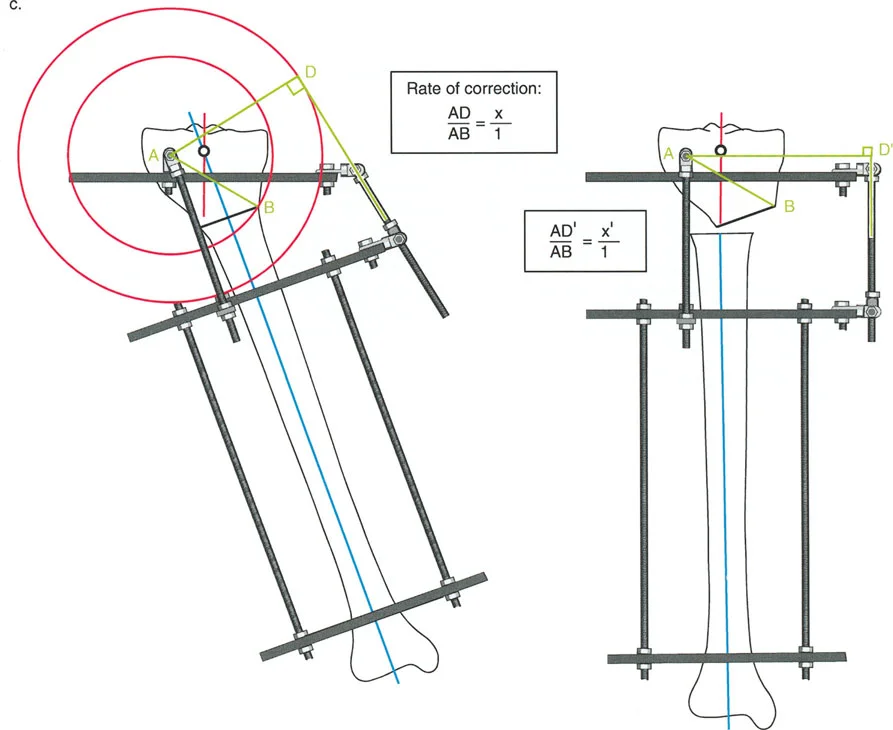

قواعد بالي لقطع العظم (Osteotomy Rules) في وضع الأجهزة

فهم قواعد بالي لقطع العظم أمر لا غنى عنه لتخطيط الإطار:

- قاعدة قطع العظم 1: عندما يمر قطع العظم ومحور تصحيح الانحراف (ACA) كلاهما عبر مركز دوران الانحراف (CORA)، فإن نهايات العظم ستنحرف دون ترجمة (انزياح). يتم استعادة المحور الميكانيكي، وتظل نهايات العظم متقاربة تمامًا، مما يخلق تصحيحًا كلاسيكيًا "إسفينيًا مفتوحًا" أو "إسفينيًا مغلقًا".

- قاعدة قطع العظم 2: عندما يمر محور تصحيح الانحراف (ACA) عبر مركز دوران الانحراف (CORA)، ولكن يتم إجراء قطع العظم على مستوى مختلف (غالبًا بسبب ضعف جودة العظم عند CORA أو مشاكل في الجلد)، فإن نهايات العظم ستنحرف وتخضع لترجمة محسوبة ومقصودة لإعادة محاذاة المحور الميكانيكي.

- قاعدة قطع العظم 3: (للاكمال) عندما يمر قطع العظم عبر مركز دوران الانحراف (CORA)، ولكن يتم وضع محور تصحيح الانحراف (ACA) خارج CORA، سيتم إنشاء تشوه ترجمة جديد، وهو خطأ شائع في وضع المفصلات غير المخطط له جيدًا.

في المنشآت القريبة من المفصل، غالبًا ما نعتمد على قاعدة قطع العظم 2. نظرًا لأنه لا يمكننا قطع العظم بأمان عند خط المفصل تمامًا (مركز دوران الانحراف CORA)، فإننا نقطع العظم في مستوى أدنى في منطقة الميتافيسيس. بعد تحقيق التصحيح الزاوي عبر المفصلات (محور تصحيح الانحراف ACA)، يتم إعادة محاذاة خطوط المحور الميكانيكي بشكل مثالي، ولكن نهايات العظم في موقع قطع العظم تتحرك بالنسبة لبعضها البعض.

إتقان معدلات الشد: قاعدة المثلثات المتشابهة

معدل 1 ملم/يوم ينطبق بشكل صارم على القشرة المقعرة للعظم في موقع قطع العظم (الحافة الأمامية للإسفين المفتوح). نظرًا لأن الجهاز (قضيب الشد أو دعامة TSF) يقع على مسافة من العظم، خارج غلاف الأنسجة الرخوة، فإنه يتحرك على طول قوس أكبر بكثير. إذا وجهت المريض لشد القضيب بمعدل 1 ملم يوميًا، فإن العظم الفعلي سيُشد بجزء ضئيل من هذا المعدل، مما يؤدي إلى التصلب المبكر لموقع قطع العظم.

حساب معدل الشد الحقيقي

لحساب المعدل الصحيح للشد عند المفصلة، نستخدم قاعدة المثلثات المتشابهة، والتي تعتمد أساسًا على القاعدة الهندسية للدوائر متحدة